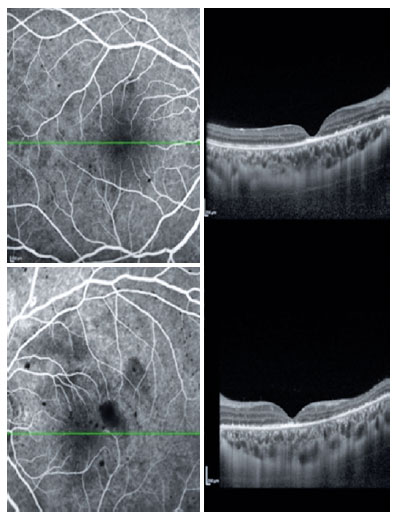

The patient was accordingly started on ceftriaxone. On the fifth day of hospitalization, the patient woke up with headache, vomiting and complaints of severely reduced visual acuity in both her eyes. A lumbar biopsy revealed presence of turbid inflammatory fluid. The ophthalmological findings were visual acuity of hand motion in both eyes and the fundoscopy revealed exudates, diffuse hemorrhages and vascular sheathing affecting the entire retina, all of which confirmed the diagnosis of FBA in both eyes (Figure 1). Cranial magnetic resonance angiography revealed areas of signal alteration in the thalamus and corpus callosum with the evidence of retinal and cerebral vasculitis.

10-fig01.jpg)